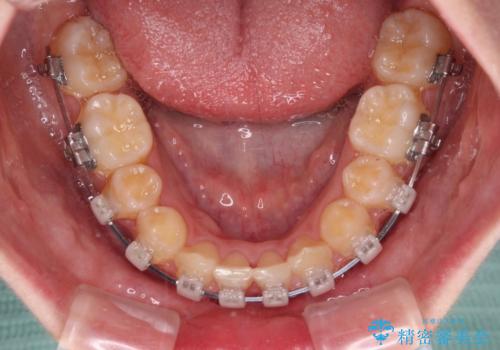

- 矯正装置

- クリアブラケット

下顎の左右側切歯2本が欠損しており、上顎歯列がデコボコとなっている状態でした。

通常の抜歯矯正と抜くべき歯の位置が異なるため、咬みにくさが残ってしまうのではないかと懸念されましたが、咬み合わせに違和感なく、スムーズに治療を終えることができました。